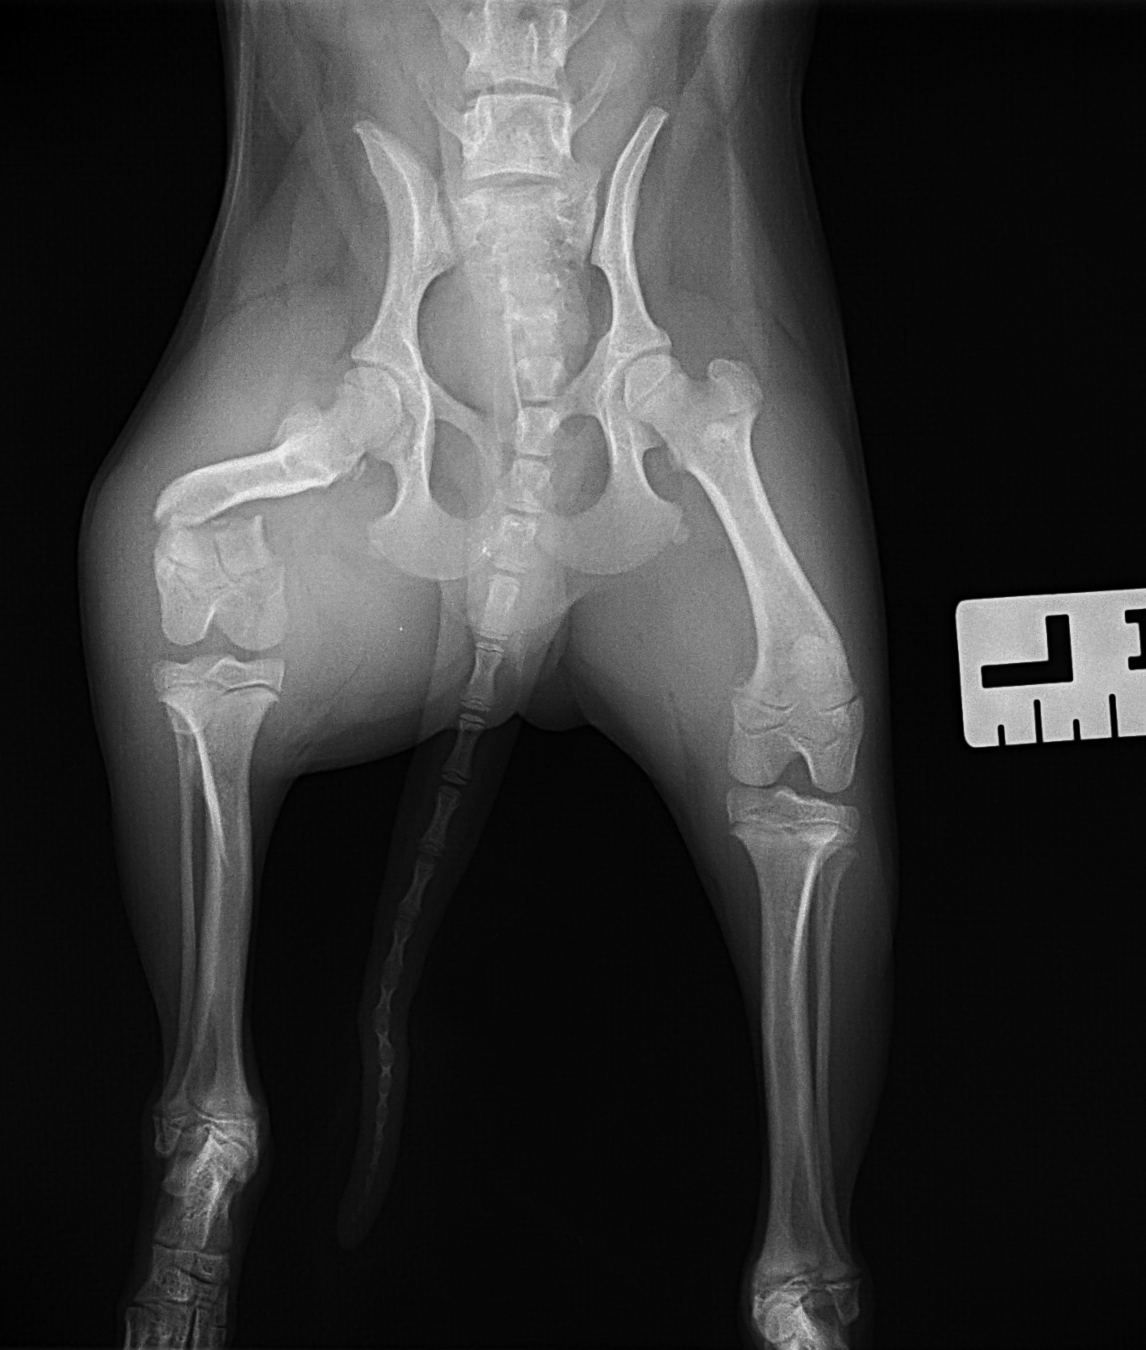

幼犬の大腿骨遠位の骨折です。幼犬は治癒能力が高く、仮骨の形成が早期に起こります。しかしながらこの時期は骨質が大変柔らかく固定には注意が必要です。本来であれば成長板をまたぐ固定は避けたいところですが、やむを得ず軽量のTitanium Locking Plateを用いて固定術を行いました。早期に抜釘することになります。